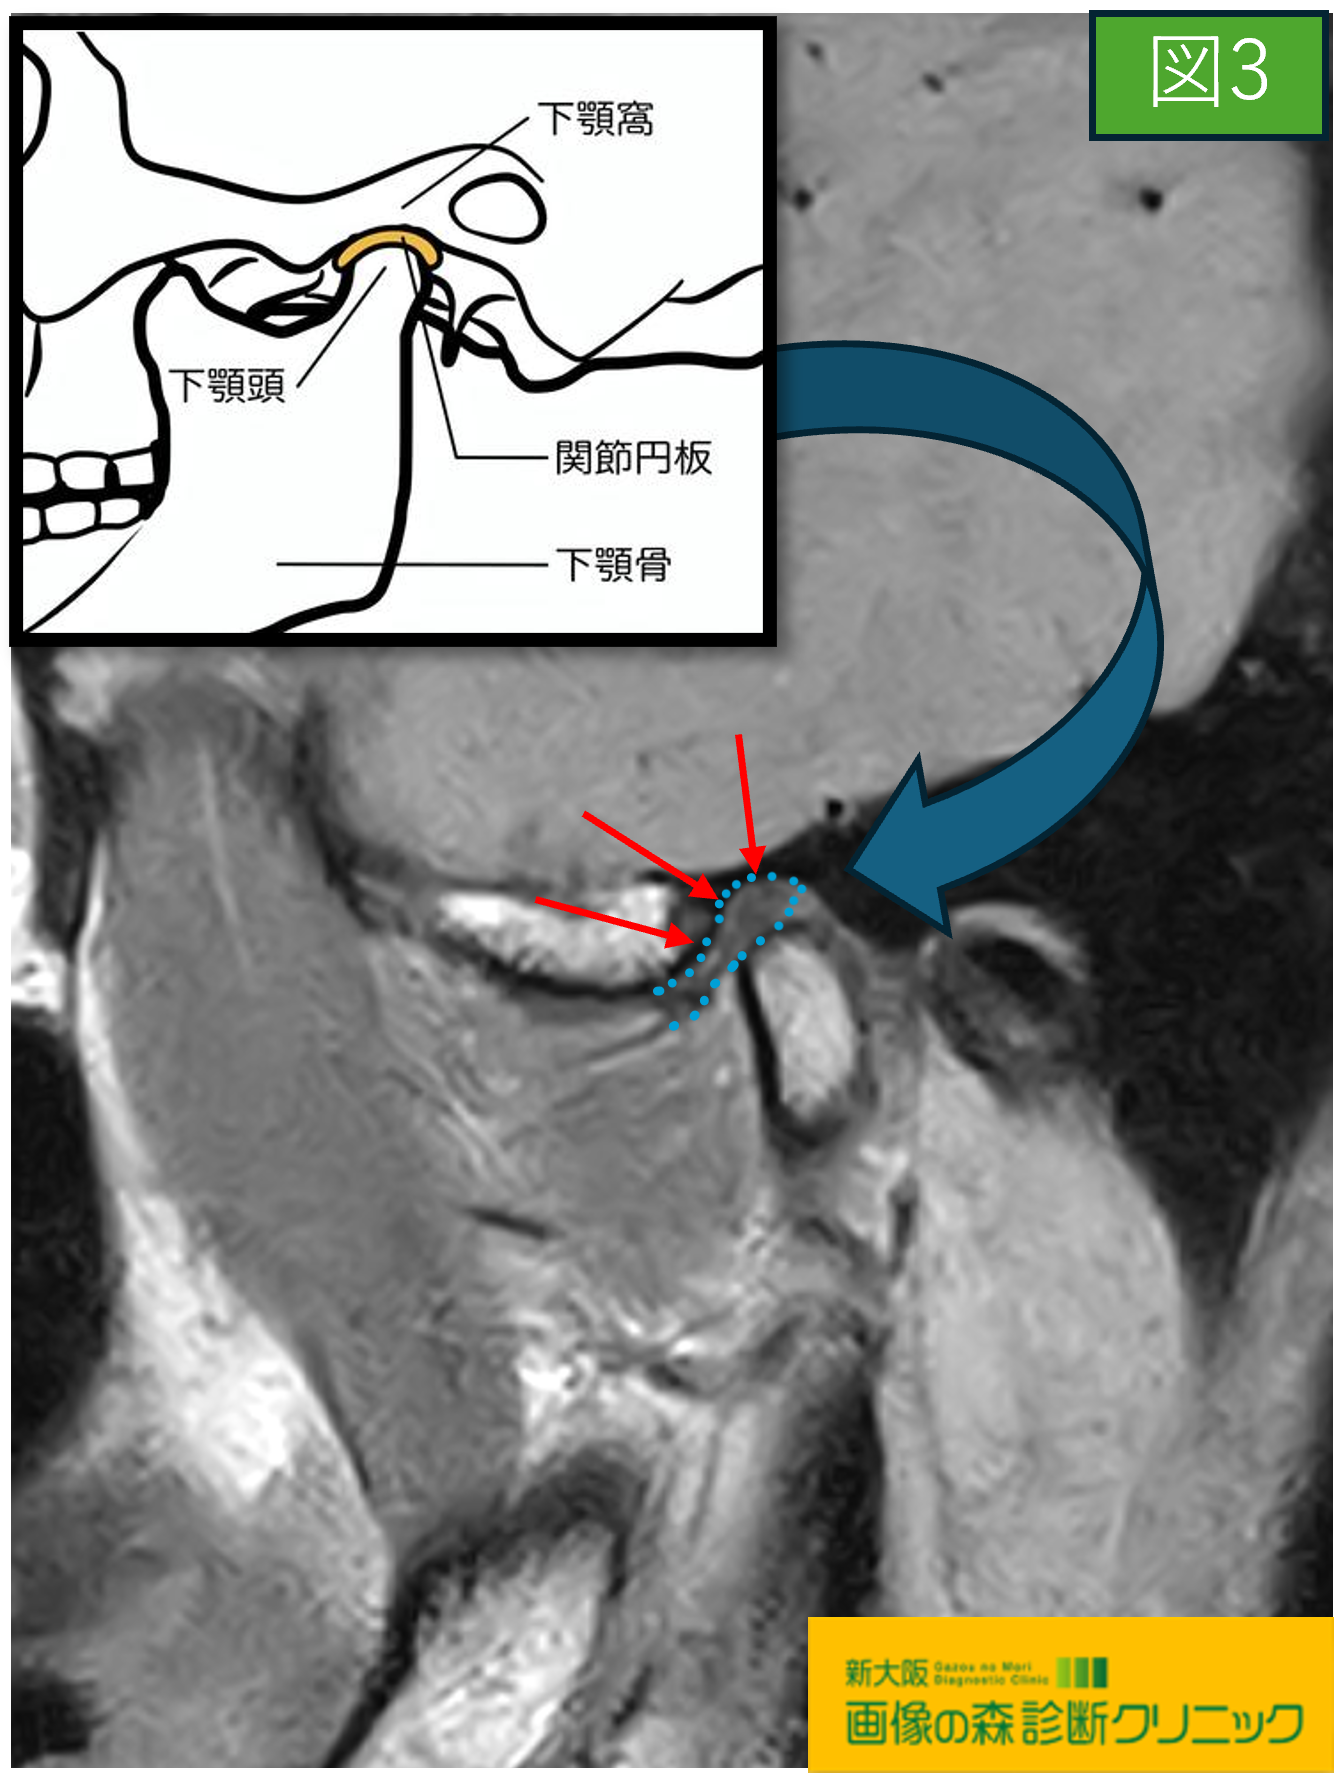

〇続けて図3・図4の画像は顎関節を横方向から観察しています

図3・図4の画像では主に関節円板に注目します。

また関節円板は、骨の間のクッションの役割があり

図3の正常画像では、関節円板(青い点線で囲っている黒色の

部分)はイラストにあるように下顎頭の真上に位置します。